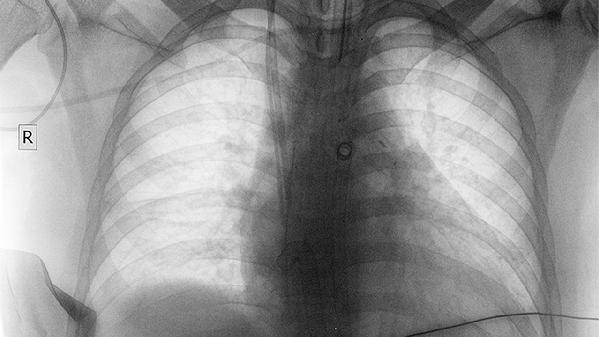

清肺散结丸含有多种抗肿瘤活性成分,能通过调节细胞周期和诱导肿瘤细胞凋亡的方式抑制肺癌细胞增殖。该药对非小细胞肺癌的抑制作用较为明显,可减缓肿瘤体积增大速度。用药期间需定期复查胸部CT评估疗效。

对于肺癌合并肺不张或胸腔积液的患者,该药可通过抗炎消肿作用改善通气功能。其利水渗湿成分有助于减少肺泡腔内渗出,降低气道阻力。但大量胸腔积液时仍需结合胸腔穿刺治疗。